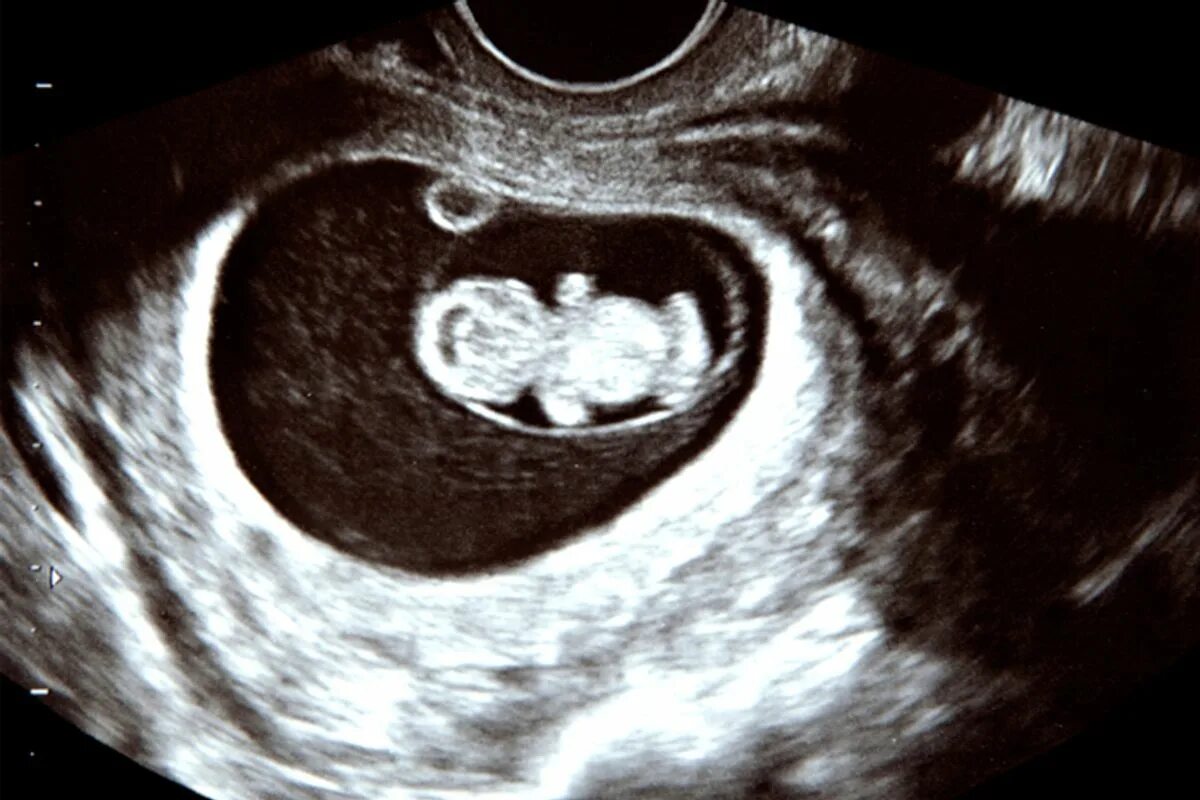

10 week old